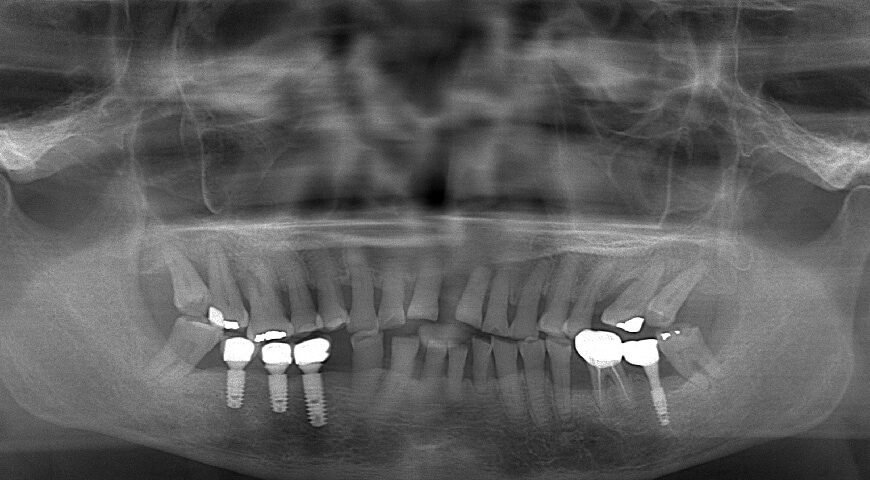

植體周圍炎是植牙最常聽到的併發症,有牙周病史的患者會有較高發生植體周圍炎的傾向。當代牙醫葉立維醫師從牙周病/植牙專科醫師的角度說明什麼是植體周圍炎、發生症狀和治療方式,並建議牙周病患者進行植牙前需先完整控制牙周病,才能避免之後發生周圍炎,讓植牙壽命維持長久。